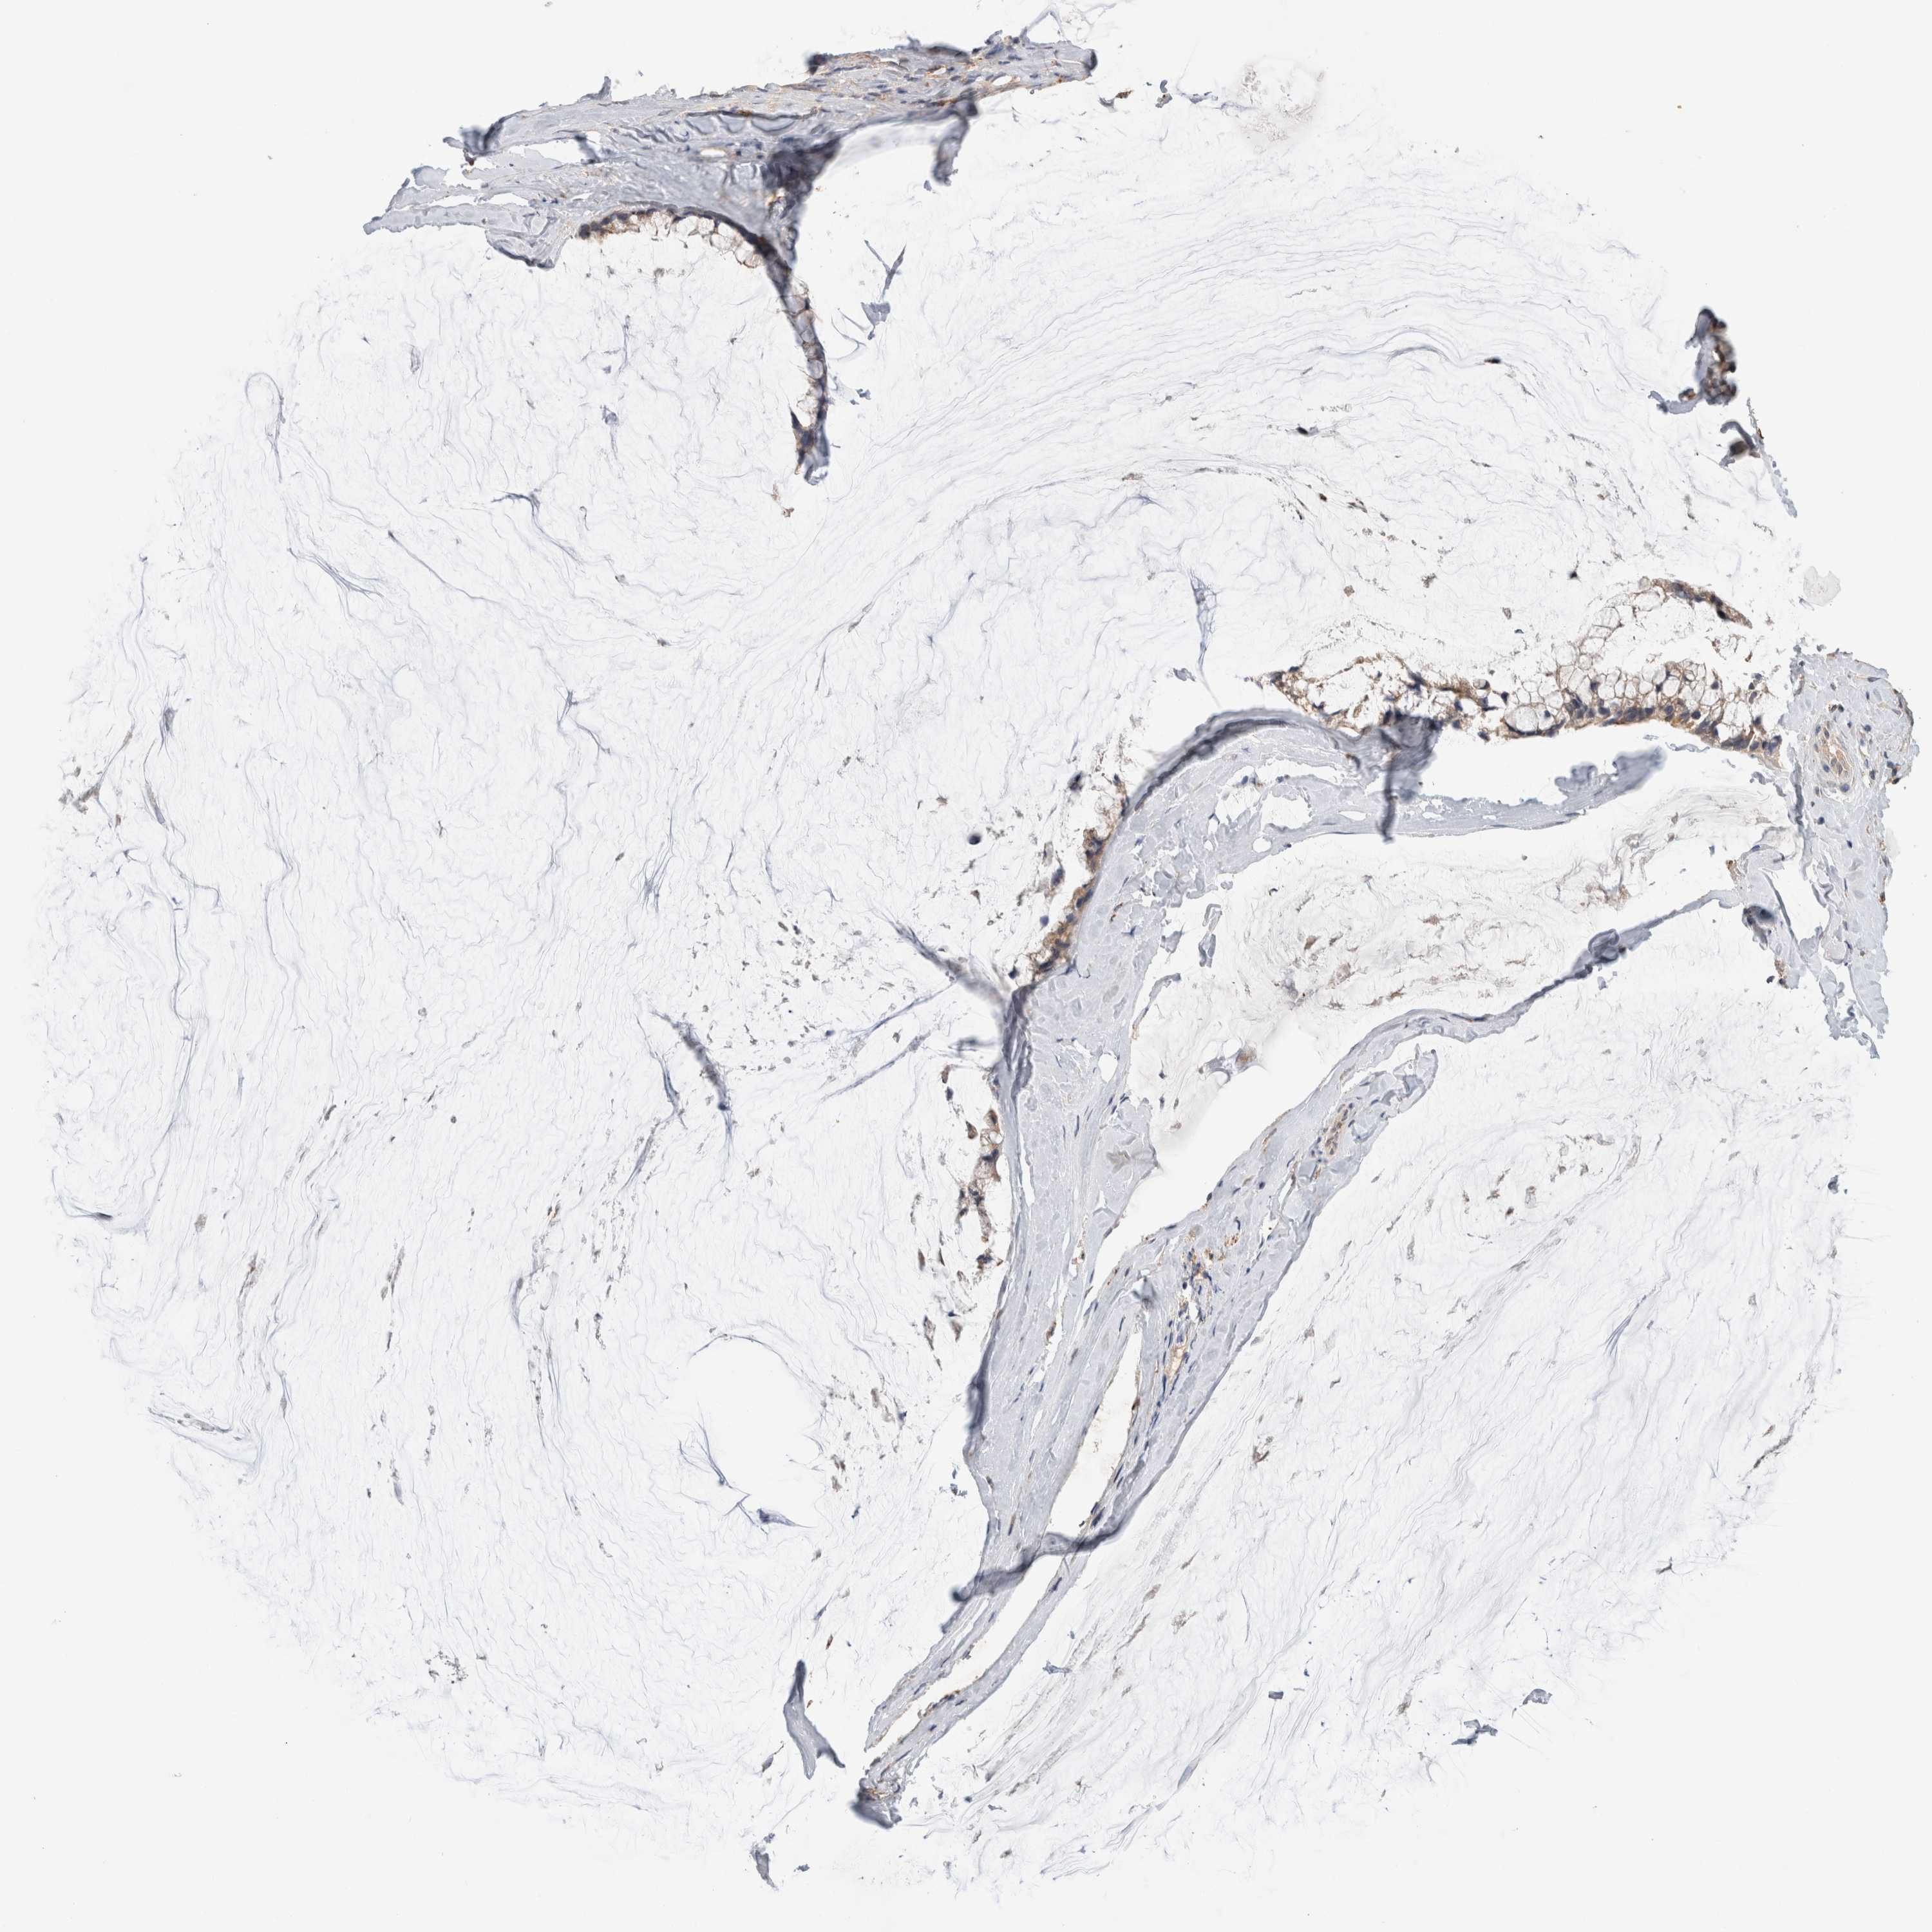

OVARIAN CANCER - Protein expressioni

A mouse-over function shows sample information and annotation data. Click on an image to view it in a full screen mode. Samples can be filtered based on level of antibody staining by selecting one or several of the following categories: high, medium, low and not detected. The assay and annotation is described here.

Note that samples used for immunohistochemistry by the Human Protein Atlas do not correspond to samples in the TCGA dataset.

Antibody stainingi

Antibody staining in the annotated cell types in the current human tissue is reported as not detected, low, medium, or high, based on conventional immunohistochemistry profiling in selected tissues. This score is based on the combination of the staining intensity and fraction of stained cells.

Each image is clickable and will lead to virtual microscopy that enables deeper exploration of all samples and also displays staining intensity scores, fraction scores and subcellular localization as well as patient and tissue information for each sample.

Antibody HPA013695

Antibody HPA048508

Antibody CAB026011

Staining

High

Medium

Low

Not detected

Cystadenocarcinoma, serous, NOS

Carcinoma, endometroid

Cystadenocarcinoma, mucinous, NOS

Carcinoma, NOS